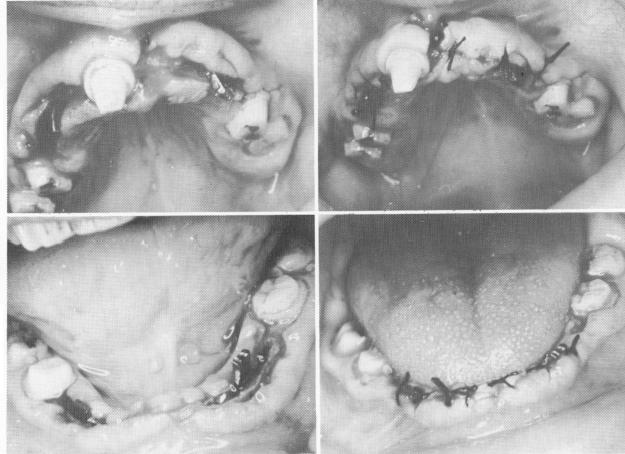

Fig. 15-86. A, Blade implants were placed into the bone on both sides of the maxilla. B, The tissues were sutured. C, Two blade implants were tapped into the mandibular bone. D, The tissues were sutured.

All remaining teeth were prepared for full coverage restorations (Fig. 15-85) . Four blade implants were carefully set into the knife-edge ridges—two in each arch   and the sites sutured closed (Fig. 15-86).

2 Two endosseous blade implants tapped into mandibular bone